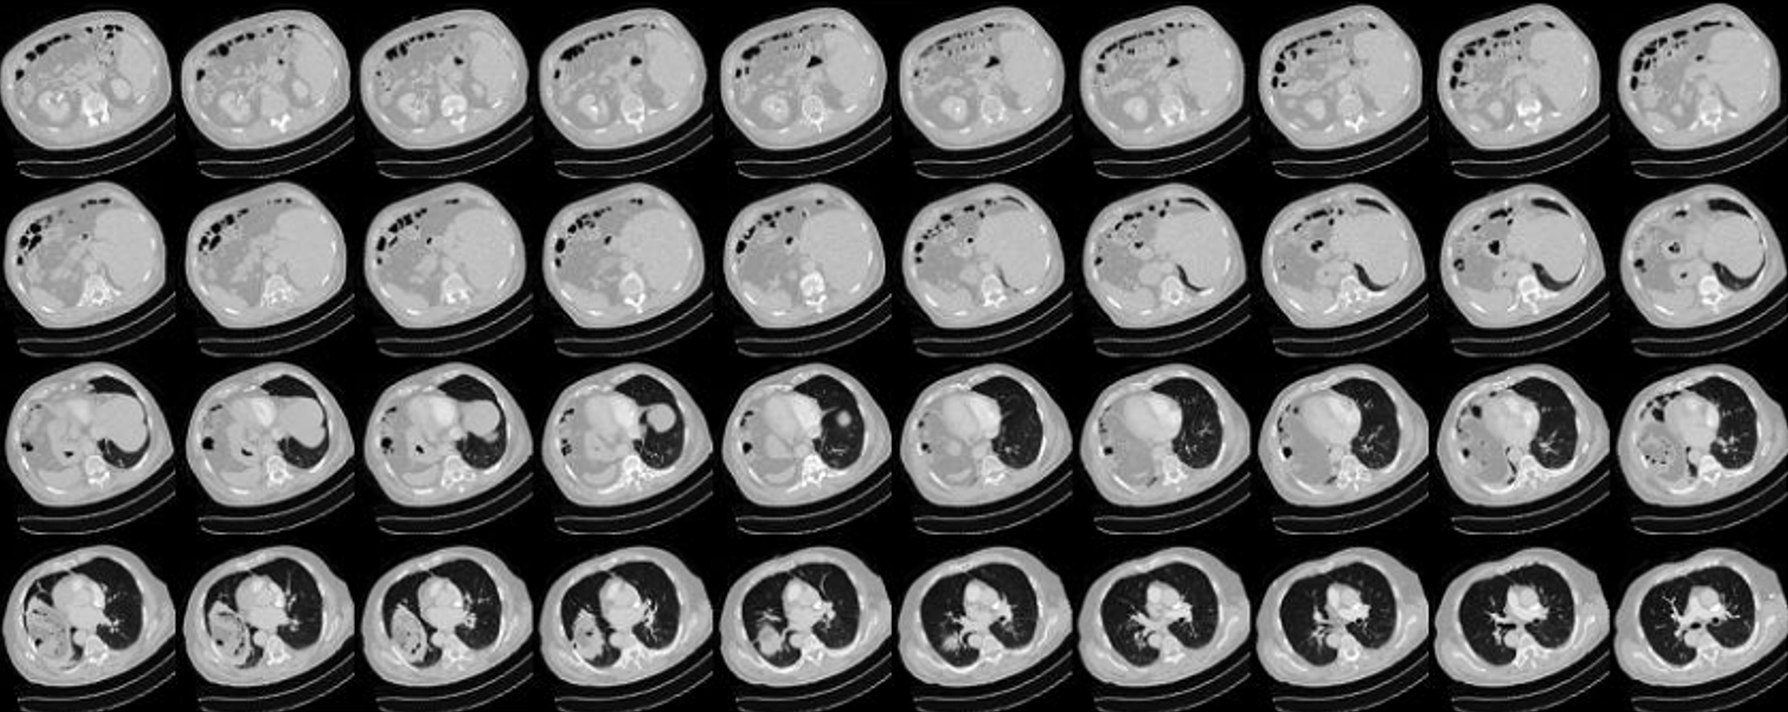

Data Source

This study utilizes a dataset provided by collaborating institutions. These datasets are sourced from the radiology department of these institutions and have been subjected to review by an Institutional Review Board (IRB) in accordance with the Personal Data Protection Act. CT scans involve the combination of X-rays and computer technology to produce cross-sectional images of the body. These images can be further processed to create detailed 3D images. Each CT scan slice has a thickness of 1 millimeter, and each patient’s scan typically consists of 100 to 300 slices, as shown in Figure 7. In total, data has been collected from 192 patients and divided into training (138 patients), validation (34 patients), and test sets (20 patients), as shown in Table 1.